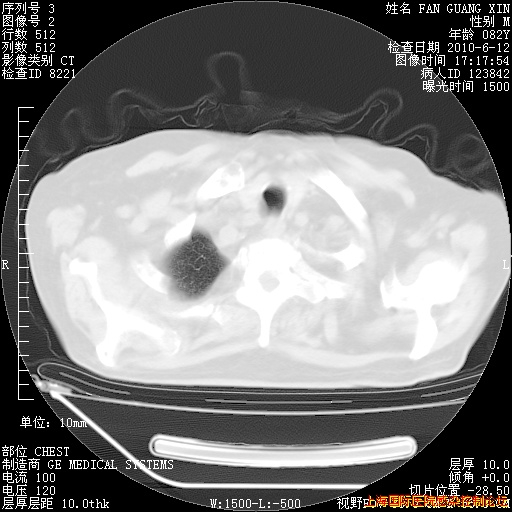

6月12日纵膈窗

整整相隔30天的肺部CT好像有所好转啊。甲强龙减量第3天,需要观察体温。

海管,自昨日你和我通完话后,不知您岳父消化道症状有无缓解?体温怎样?阅读7.12日胸部ct,个人认为目前激素治疗是有效的,甲强龙减量是适宜的。因在抗痨治疗,需密切观察肝功、肾功能和血常规。不过,老年、长期住院和大量使用激素,很担心菌群失调发生